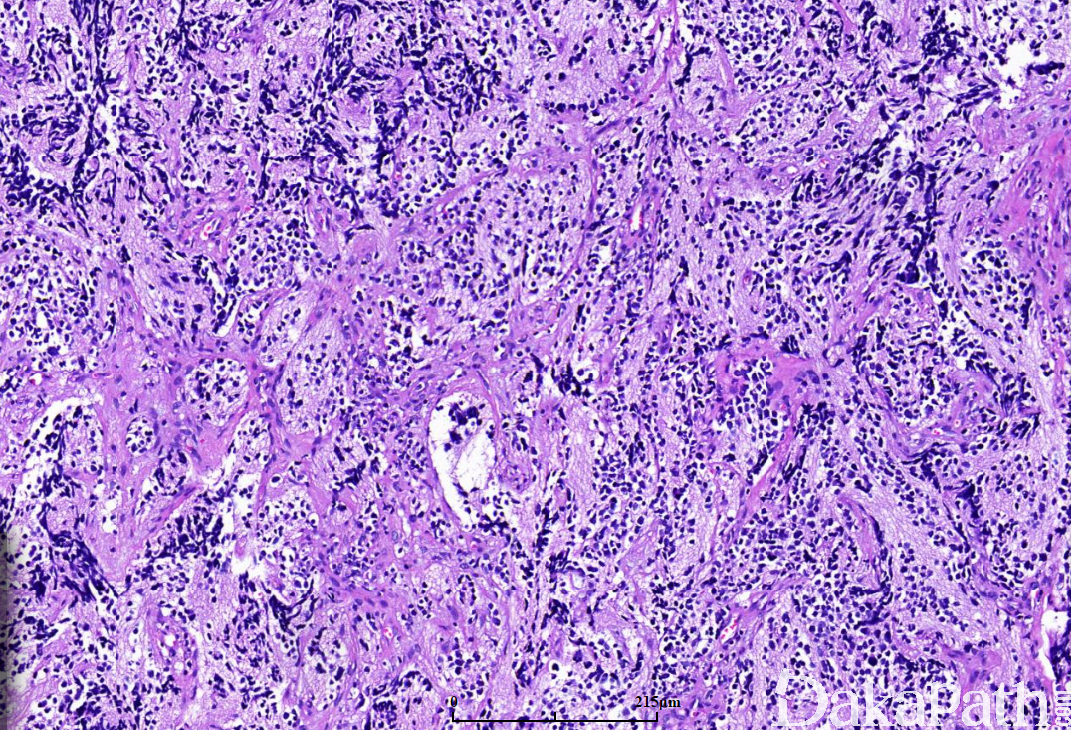

在未分化型的神经母细胞形态学基础上,在局灶区域或明显可见神经纤维网(神经毡)和(或)Homer-Wright 菊形团(约 30%):1 层或数层神经母细胞围绕中央的神经毡性间质呈放射状排列;

瘤细胞核染色质呈粉尘状或点彩状,神经节细胞分化< 5%;

肿瘤间质内含有大量的神经纤维网(神经毡),神经节细胞分化超过 5%;

纤维血管间质或间隔内常见梭形施万细胞性间质,但< 50%肿瘤比例,多位于肿瘤的周边区域;